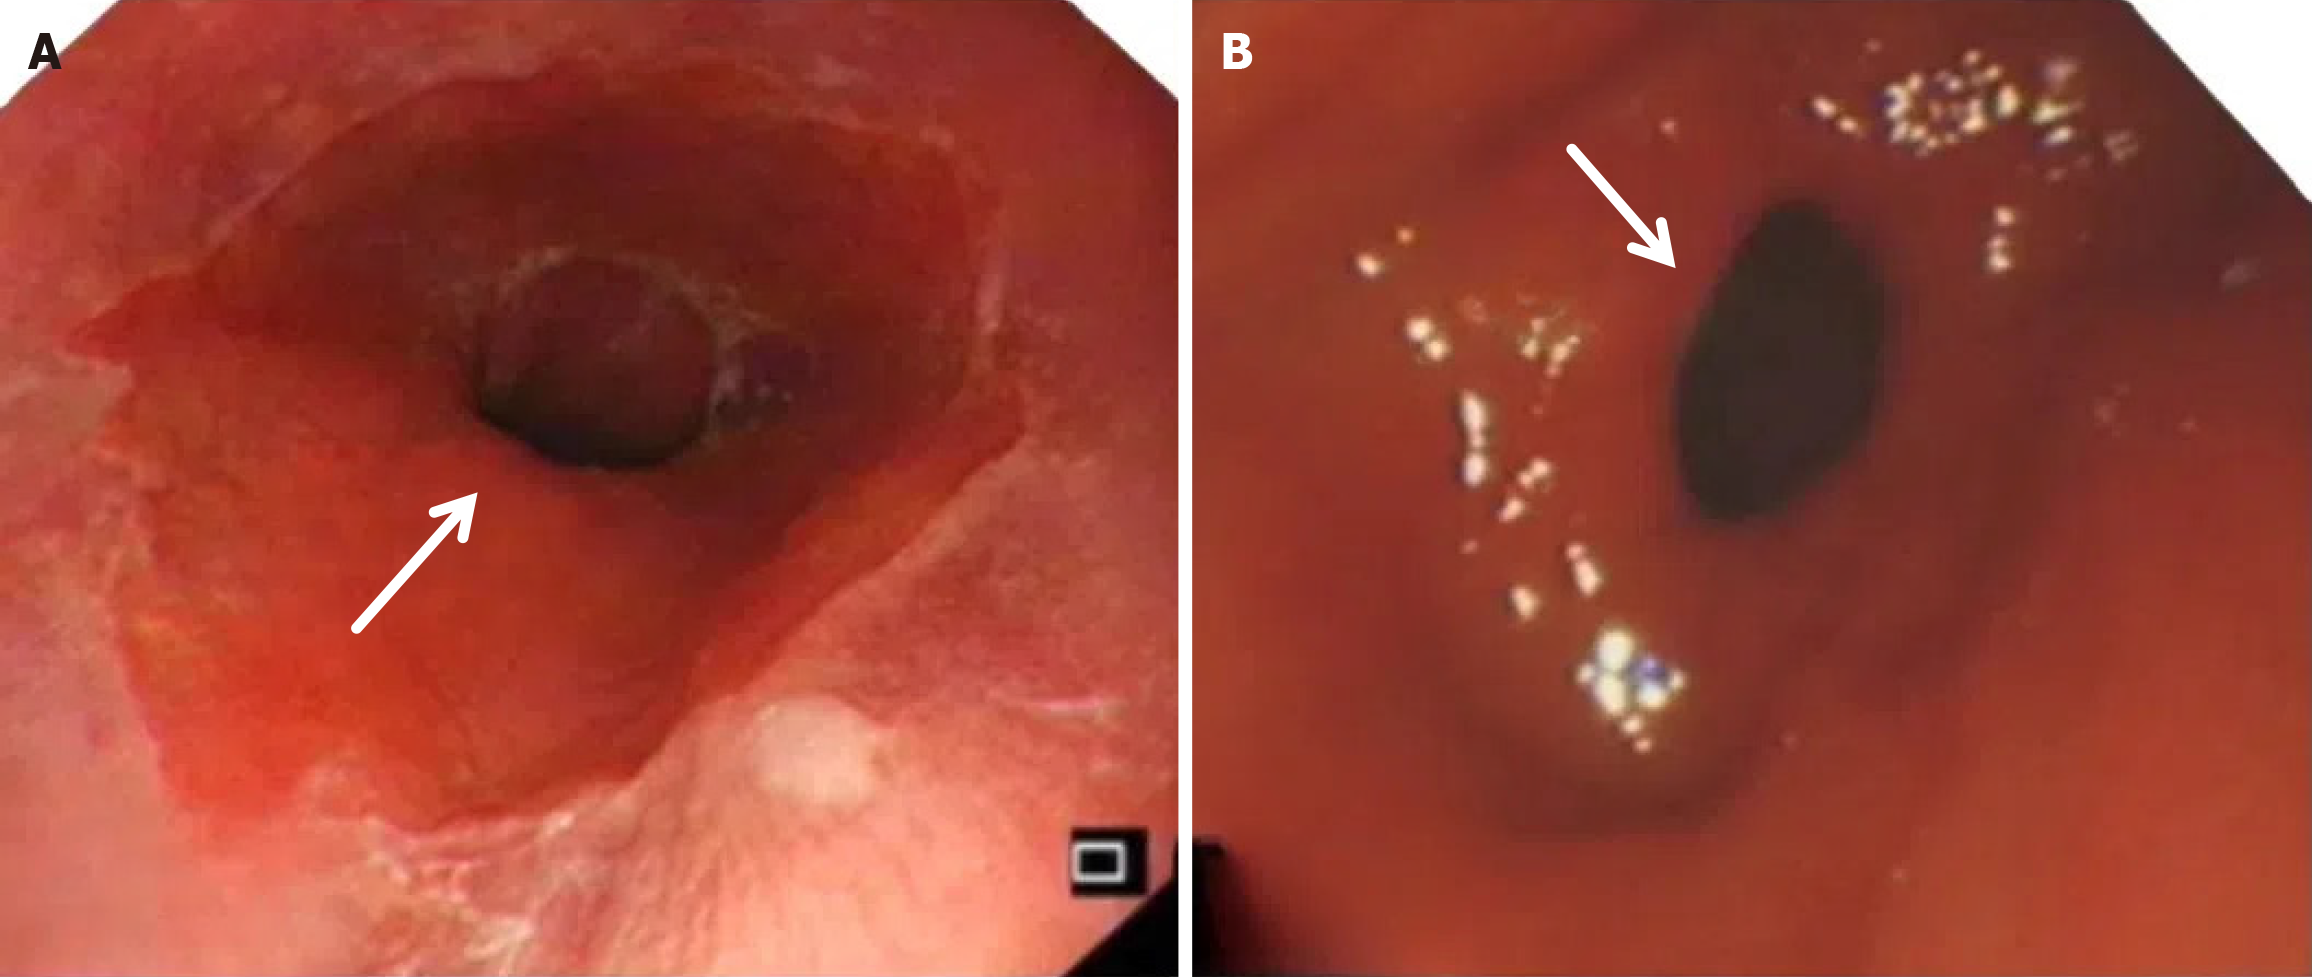

Compared with the modified group, the Orr group had a greater incidence of anastomotic leakage (AL) and short-term complications of anastomotic ischemia, although there was no significant difference between the two groups. Furthermore, Fisher’s exact probability analysis revealed that the incidence of reflux esophagitis, anastomotic ulcers by endoscopic examination, and intestinal obstruction in the Orr group was greater than that in the modified group at the 6-month postoperative follow-up period (P < 0.05) (Tables 3, 4 and 5).

There was no significant difference in weight loss between the two groups at 1 month after the operation (P > 0.05). However, in the improved group, the weight of the improved group was less than that of the original group at 3 months and 6 months after the operation (P < 0.05). The hemoglobin in the Orr group decreased significantly at 1 and 3 months after the operation compared with that in the improved group (P < 0.05), but there was no significant difference between the two groups at 6 months after the operation (P > 0.05). There was no significant difference in total protein or serum albumin between the two groups at 1 month, 3 months, and 6 months after the operation (P > 0.05) (Figures 2, 3, 4, 5 and 6, Table 6).

After total gastrectomy, due to the loss of antireflux function of the cardia, the reverse peristaltic wave generated by the pacing cells of the duodenum leads to the reflux of food and bile into the esophagus, resulting in clinical symptoms such as reflux esophagitis and other gastrointestinal duct discomfort[21]. Previous studies have shown that the jejunal storage bag after total gastrectomy can effectively relieve the pressure of food passing through the esophagojejunostomy. When food flows back from the distal output loop, the storage bag has a similar “siphon effect” to play an antireflux role and reduce the incidence of reflux esophagitis[22]. The antireflux effect is positively proportional to the length of the jejunal storage bag; nevertheless, a storage bag that is too long increases the incidence of Roux stasis syndrome, and the ideal length is approximately 5 cm[23]. In our study, storage bags with a length of approximately 5 cm were constructed at the anastomosis of the esophagus and jejunum in both groups. Our results revealed that the incidence of reflux esophagitis in the Orr group was greater than that in the improved group (P < 0.05), which occurred because the jejunal storage bag was constructed after the jejunum and its mesentery were disconnected, and the residual end of the storage bag lacked traction of the mesentery in the Orr group; therefore, the “siphon effect” was weakened. By contrast, the storage bag of patients in the improved group only needed to disconnect the jejunum, and the jejunal mesentery was continuous, resulting in strong negative pressure suction.